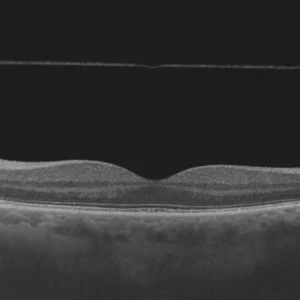

Tomographie en Cohérence Optique

Université de Toulouse